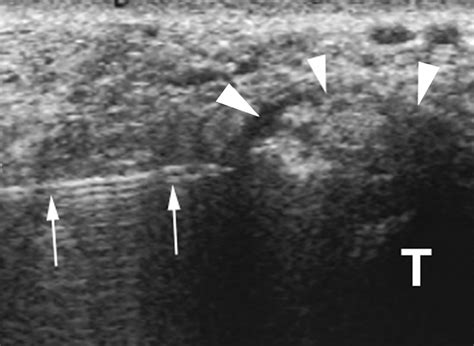

Imaging tests, such as X-rays, MRI, or CT scans, can provide detailed images of the ankle joint and surrounding structures. These tests can help identify any abnormalities, such as bone spurs, fractures, or soft tissue damage, that may be contributing to the symptoms.